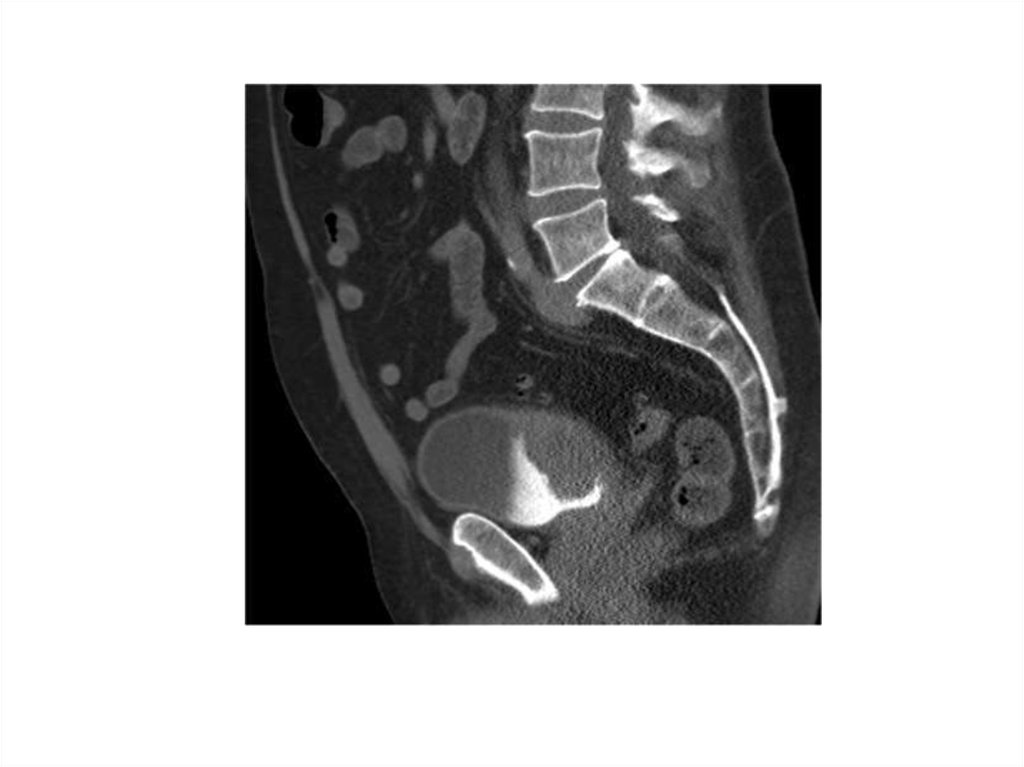

29. How is it Diagnosed?

Diagnostics

• Cystoscopy

• Tissue sample

• Radiologic Tests

• CT scan

• Stage & Grade